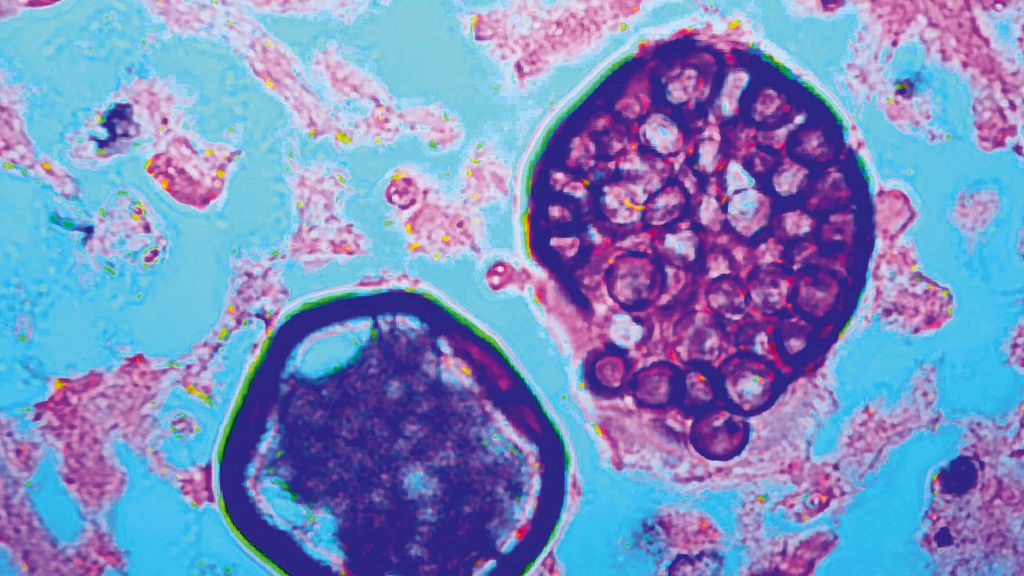

Seltene pulmonale Mykosen: Reisemitbringsel oder doch schon heimisch?